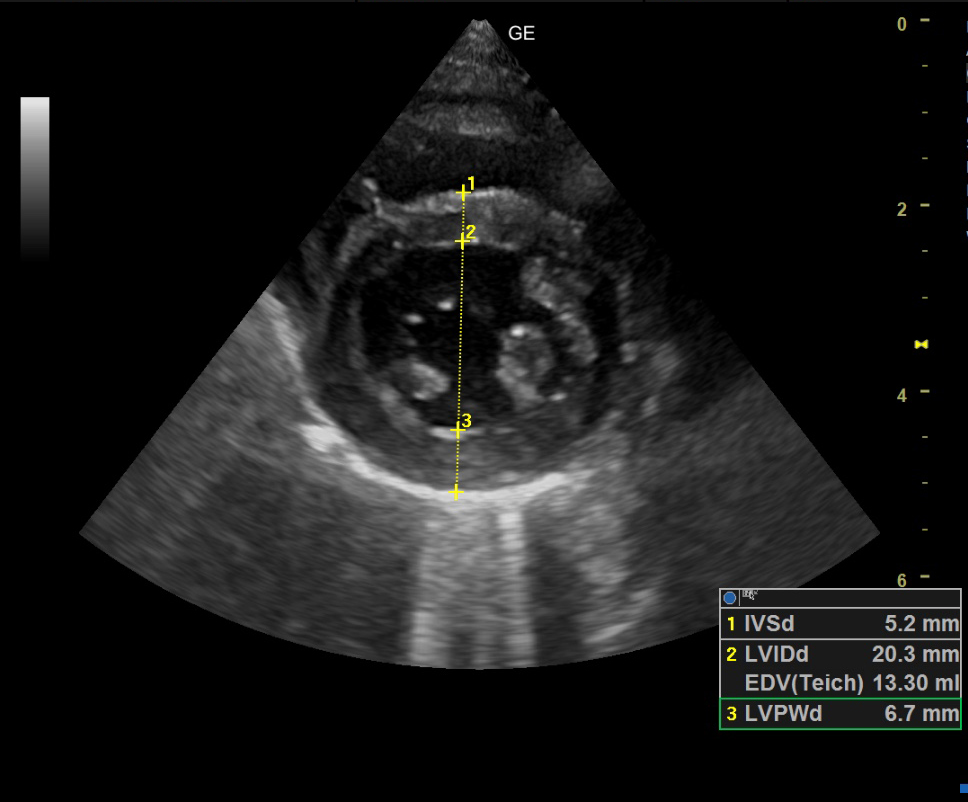

心エコー検査

心エコー検査では、超音波を用いて心臓の形態や動きをリアルタイムで観察できます。

心エコー検査は、

- 心臓の大きさ

- 心臓の壁の厚さ

- 弁の状態

- 血流の様子

などを詳細に評価できます。

非侵襲的で痛みを伴わず、短時間で行えるため、循環器疾患の診断に欠かせない検査です。

猫の肥大型心筋症

猫の肥大型心筋症は心臓の筋肉が厚くなることで心臓の動きが障害され、全身に十分な血液を送り出せなくなる病気です。 肥大型心筋症は特定の猫種において発生しやすいことが知られています。特にメインクーンやラグドールなどの純血種に多く、遺伝的要因が関与していると考えられています。 猫の肥大型心筋症は、初期段階ではほとんど症状が現れないため、飼い主様が気づくことは難しいです。 しかし、病気が進行すると、呼吸困難や突然倒れてしまうなどの重篤な症状が現れることがあります。 肥大型心筋症は早期発見が難しいため、定期的な健康診断がおすすめですね。 健康診断では血液検査だけではなく、レントゲン検査や心エコー検査といった画像検査も行うことで病気の早期発見につながります。 当院ではこれらの検査を通じて猫の心臓の状態を正確に把握し、適切な治療方針を立てることができます。